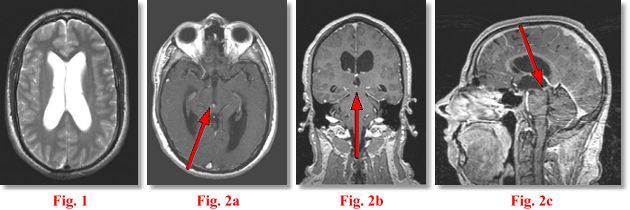

IMAGING FINDINGS: The study was performed on AIC’s high-field Siemens Symphony scanner. Fig. 1 shows an axial T2 weighted image of the ventricles demonstrating moderate hydrocephalus. Fig. 2a-c are post-contrast axial (5 mm), coronal (1 mm) and sagittal (1 mm) T1 weighted images through the aqueduct. They demonstrate a subtle tiny 4 mm enhancing mass (arrows) at the entry zone into the aqueduct at the junction with the inferior 3rd ventricle.

DIFFERENTIAL DIAGNOSIS: This is a solid mass in the ventricular system. The following DDX was rendered at the time of the scan: meningioma, ependymoma, subependymoma, PNET, a vascular lesion or, less likely, a glioma or metastasis.

PATHOLOGIC DIAGNOSIS: Pathology revealed a PINEOCYTOMA, obviously in an ectopic location as the tumor was away from the pineal gland, which is posterior to the 3rd ventricle. Final Diagnosis: Ectopic Pineocytoma.